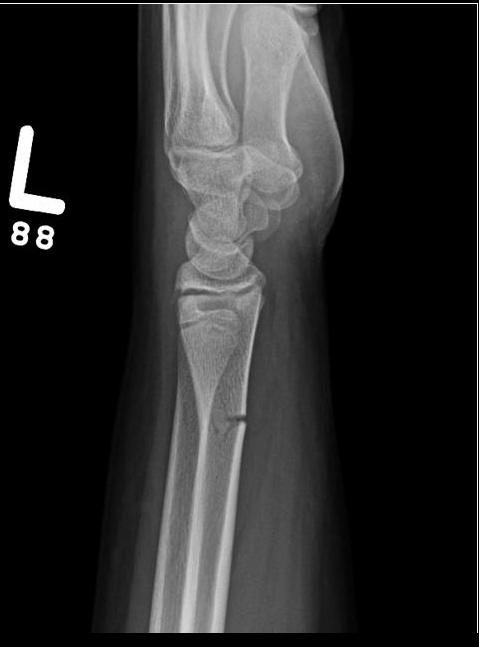

Greenstick

A Greenstick fracture is an incomplete fracture of long bones that is commonly seen in children. The bone bends and cracks but does not break into pieces, largely due to the softness and flexibility of bones in children.

These fractures occur when the bone is bent and there is failure on the tensile (convex) side of the bone. This is different than in torus fractures where the concave side buckles.

The fracture line does not propagate to the concave side of the bone, but the concave side shows evidence of microscopic failure with plastic deformation.

X-ray imaging will show a mid-diaphyseal break, usually with angulation and disruption of the cortical bone on the side of the fracture.

It may be necessary to break the bone on the concave side in order to achieve reduction of the fracture because the plastic deformation recoils it back to the deformed position. Immobilization with casting for 2-3 weeks allows this fracture to heal.